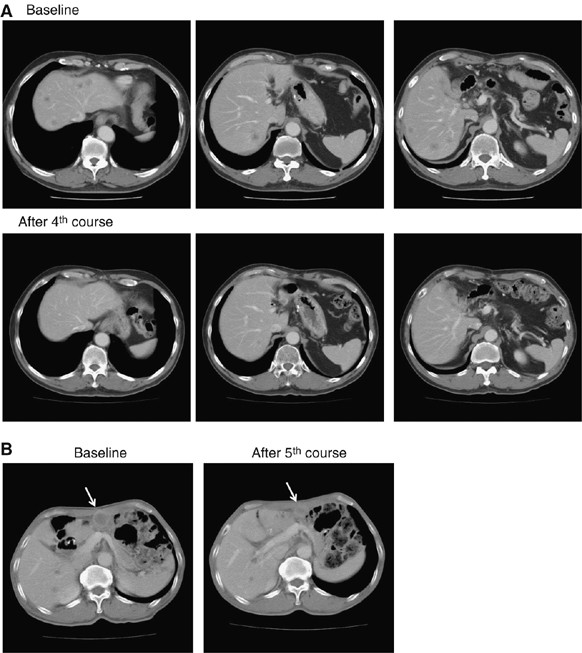

Figure 3

Serial CT scans. (A) A 60-year-old male with pancreatic cancer who was treated with NK105 at a dose level of 150 mg m−2. Baseline scan (upper panels) showing multiple metastasis in the liver. Partial response, characterized by a more than 90% decrease in the size of the liver metastasis (lower panels) compared with the baseline scan. The antitumour response was maintained for nearly 1 year. (B) A 64-year-old male with stomach cancer who was treated with NK105 at a dose level of 150 mg m−2. Baseline scan (left panel) showing a peritoneal metastasis and liver metastasis. About 40% reduction (right panel) was observed in peritoneal metastasis, but not in the liver metastasis after fifth course.